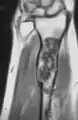

MRI showing enchondromas localized in the lower part of the radius of a 37-year-old patient affected with Ollier disease.

Enchondromas localized in the upper part of the humerus of the same patient